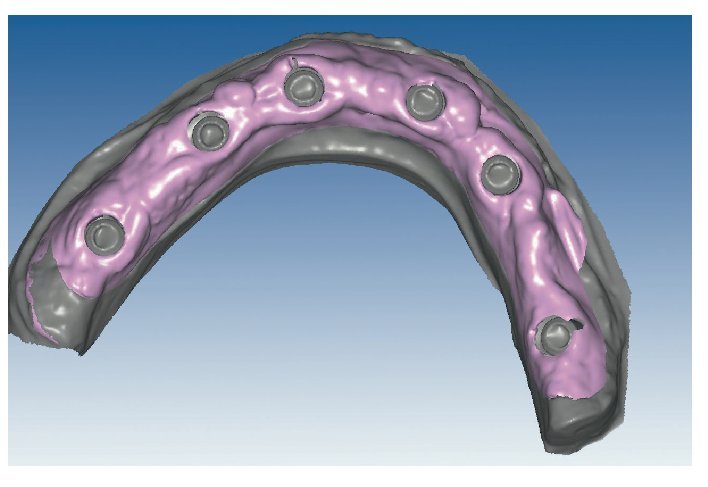

Mediante el uso de un escáner óptico de luz estructurada, los protocolos CAD registran los primeros datos relativos al modelo maestro con las correspondientes posiciones de implante (figs. 87 y 92). En el siguiente paso tiene lugar la digitalización de la planificación, previamente realizada en cera de escaneo matificada, de la restauración definitiva (figs. 88, 90 y 93). La subsiguiente conciliación de los datos mediante el uso del software de diseño dental permite al protésico planificar virtualmente el resto del procedimiento (figs. 89 y 91, 94 a 96) a partir del diseño de las estructuras (figs. 97 y 98).

Fig. 87. Imagen CAD del modelo maestro superior.

Fig. 90. La posición de los implantes en relación con la planificación.

Fig. 91. El diseño definitivo de la estructura para el maxilar superior.